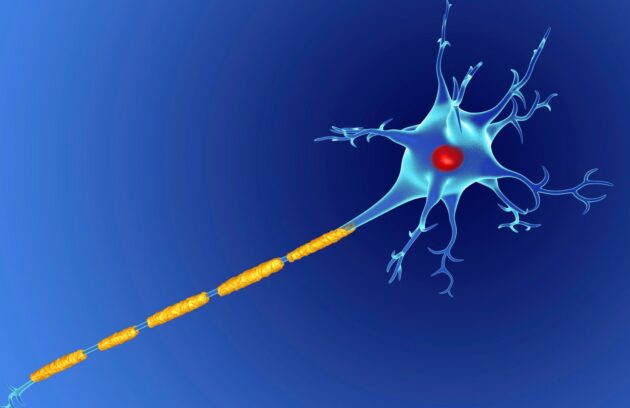

Biorezonans ile MS Tedavisi

Biorezonans ile MS tedavisi Multiple skleroz (MS) inflamasyon, miyelin (sinir kılıfı) ve akson hasarı ile seyreden otoimmün bir merkezi sinir…